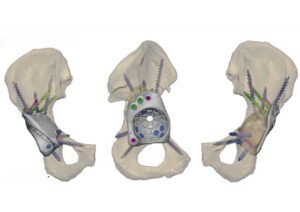

In close collaboration with the surgeon, the Jajal Medical design team initiated a detailed preoperative planning process.

- Advanced CT imaging and 3D segmentation were used to precisely map the patient’s bone anatomy.

- Based on the defect morphology, a patient-specific FTL cup was engineered to provide maximum coverage and optimal load distribution.

- Virtual prototypes of the implant were shared with the surgeon for review, ensuring accuracy and clinical confidence before manufacturing.

Key Features of the Custom FTL Cup:

- Custom geometry tailored to fit the patient’s acetabular defect

- Porous lattice structure at the bone-implant interface to promote long-term osseointegration

- Optimized screw trajectories for enhanced fixation in available host bone

- Dedicated drilling guides are supplied to ensure accurate screw placement during surgery